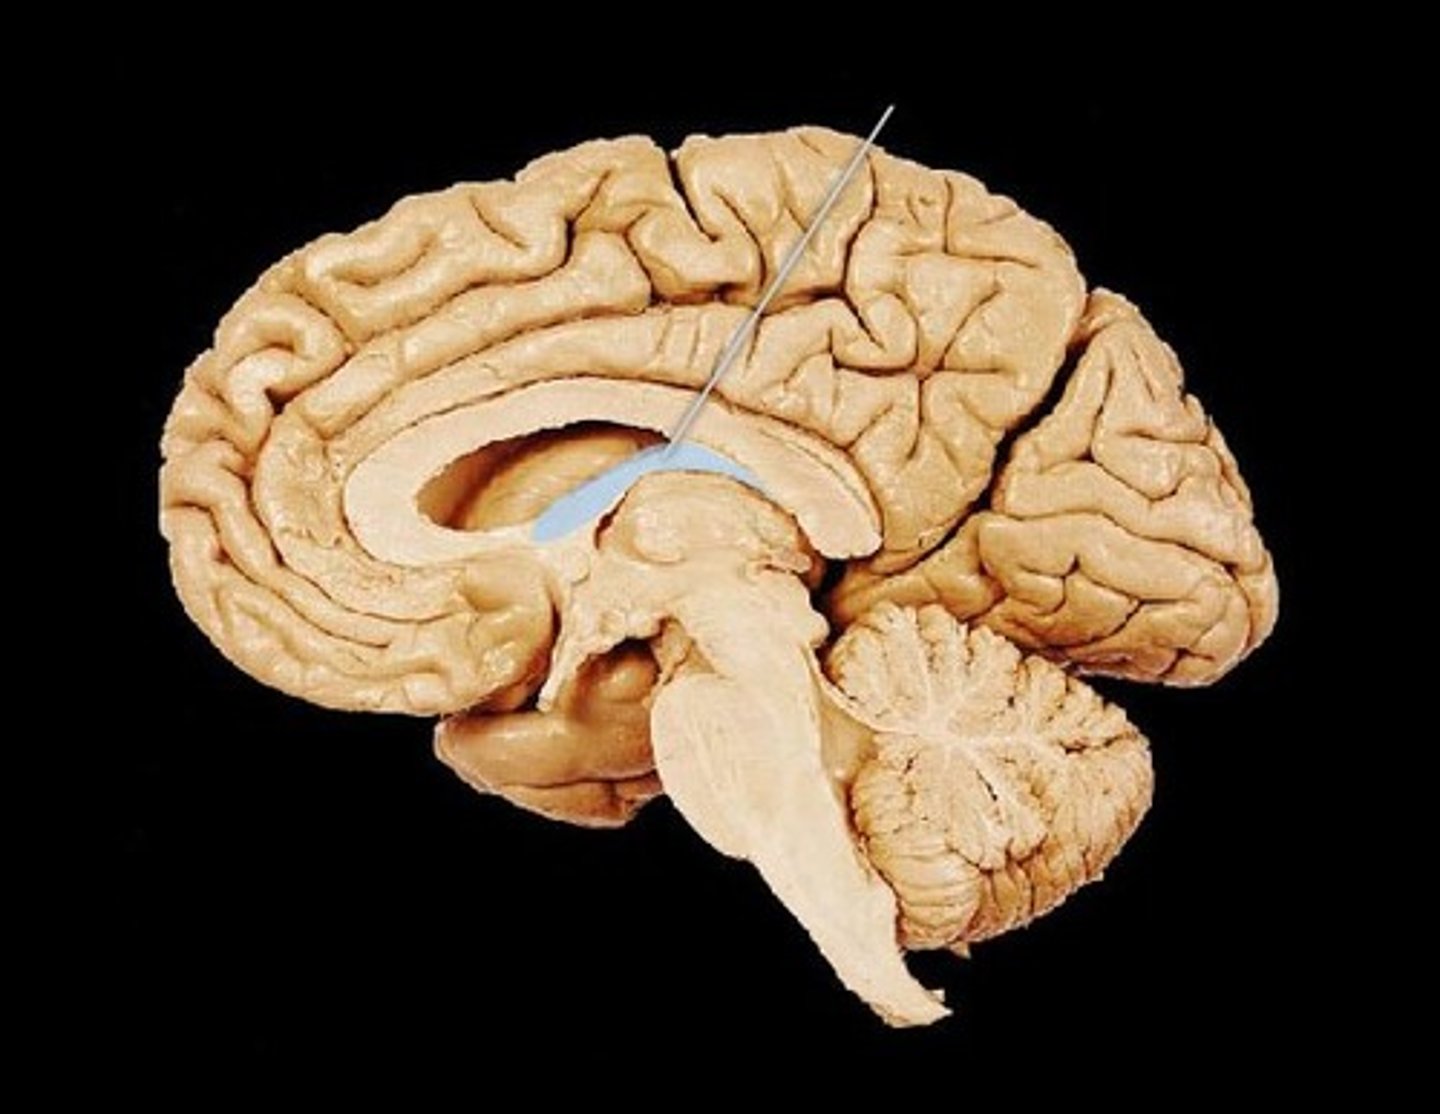

Corpus Callosum

Fibers connecting both halves of the brain, c shaped structure

Fornix

fiber tract linking limbic system regions

Cerebellum

"little brain" attach to the top of the brain stem. Components include vermis, arbor vitale, cortex, peduncles

Brain Stem

Continuation of spinal cord. Contains medulla oblongata, pons and midbrain

Pons

bulging brain stem region between midbrain and medulla.

Medulla Oblongata

most inferior part of brain stem, eventually becomes spinal cord. Autonomic reflex center.